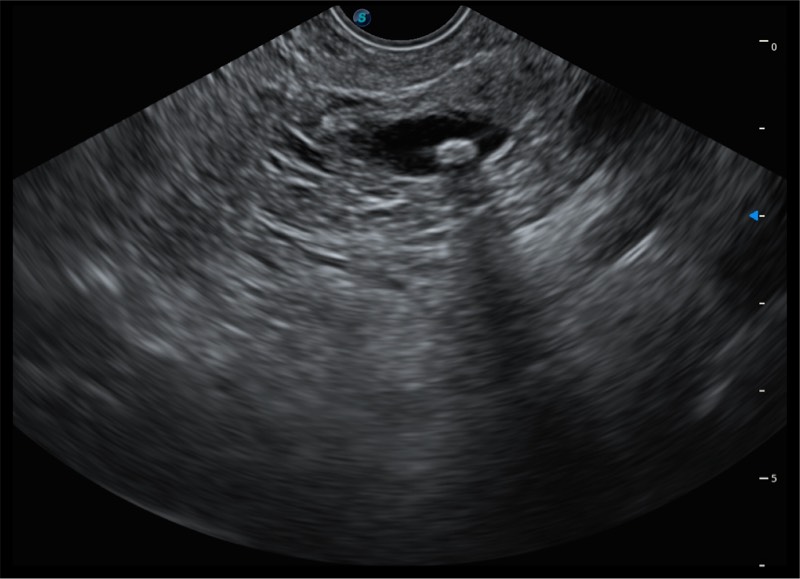

搭载百万级CMOS成像技术

及自主研发凸阵换能器,

可呈现优质的内镜和超声画面

基于二十年的超声技术积累,环球UG官网提供了最新一代的独立超声主机,在提供高质量图像的同时满足多学科使用。具备常见多普勒技术并提供弹性成像、声学造影等高端影像技术。新一代传感器具有更强的抗干扰能力并减少图像伪影。

4-12MHZ宽频输出